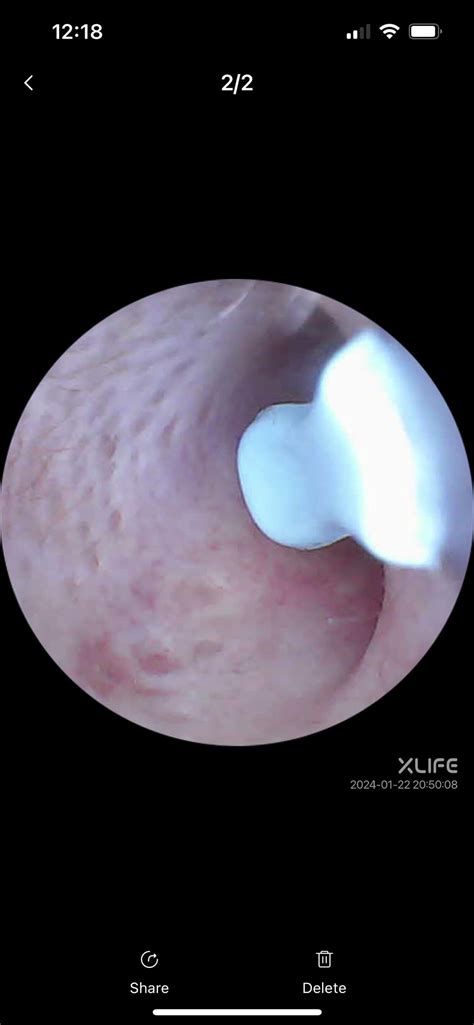

Tools for Spotting Inside Ear Canal

Several tools are available to help you spot inside ear canal and assess the condition of your earwax. These tools are designed to be safe and effective for home use. Some of the most commonly used tools include:

• Otoscope: A medical device used by healthcare professionals to examine the ear canal and eardrum. It provides a clear view of the ear canal and can help identify the presence and location of earwax.

Step 3: Use the Otoscope or Earwax Removal Kit

Use the otoscope or earwax removal kit to spot inside ear canal and assess the condition of the earwax. Gently insert the tool into the ear canal and use the light source to get a clear view. Be careful not to insert the tool too deeply, as this can cause damage to the eardrum.